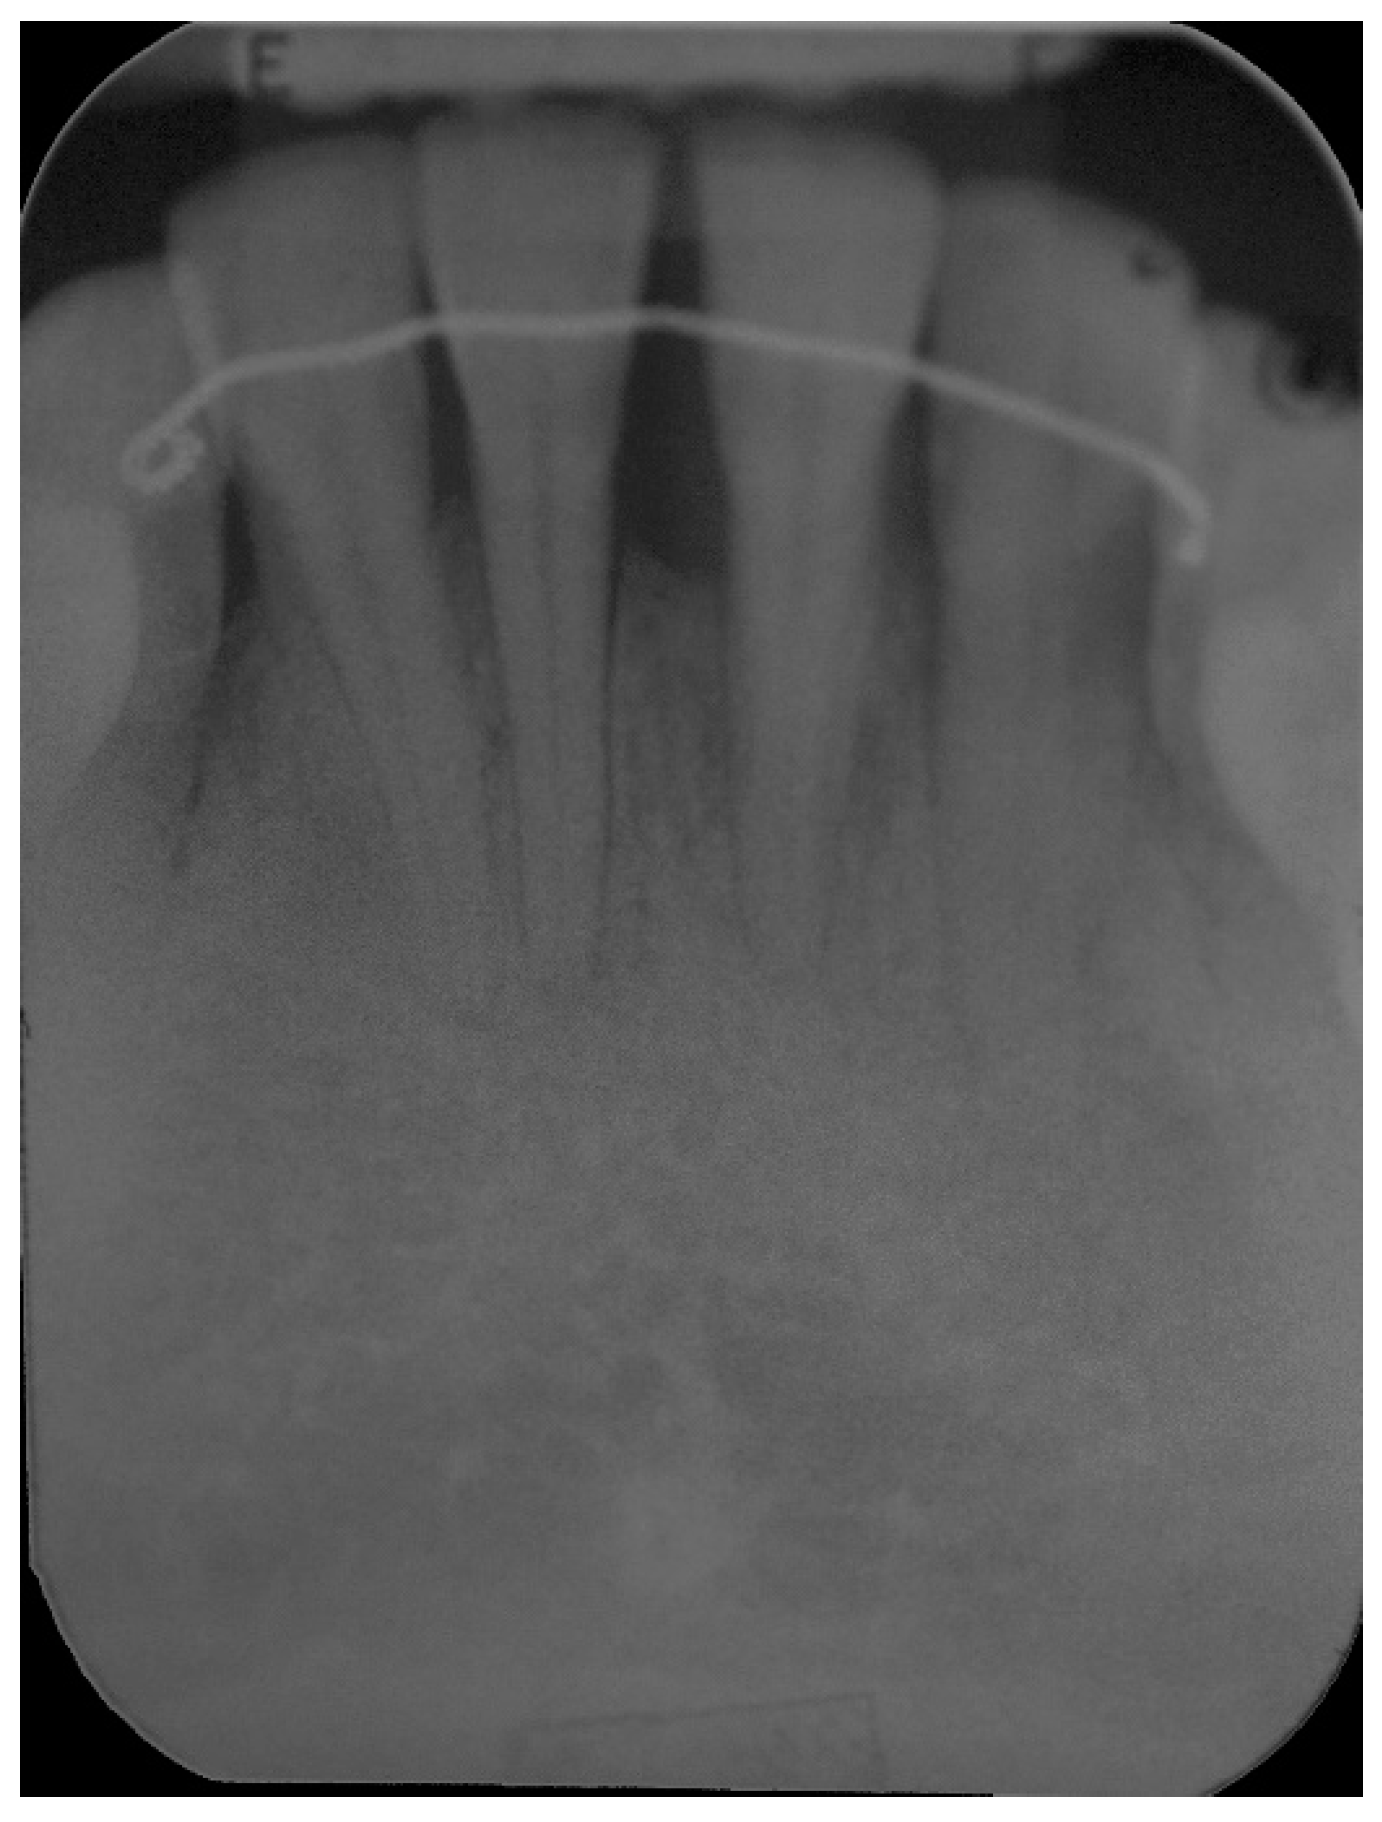

5. Materials and Methods

6. Results